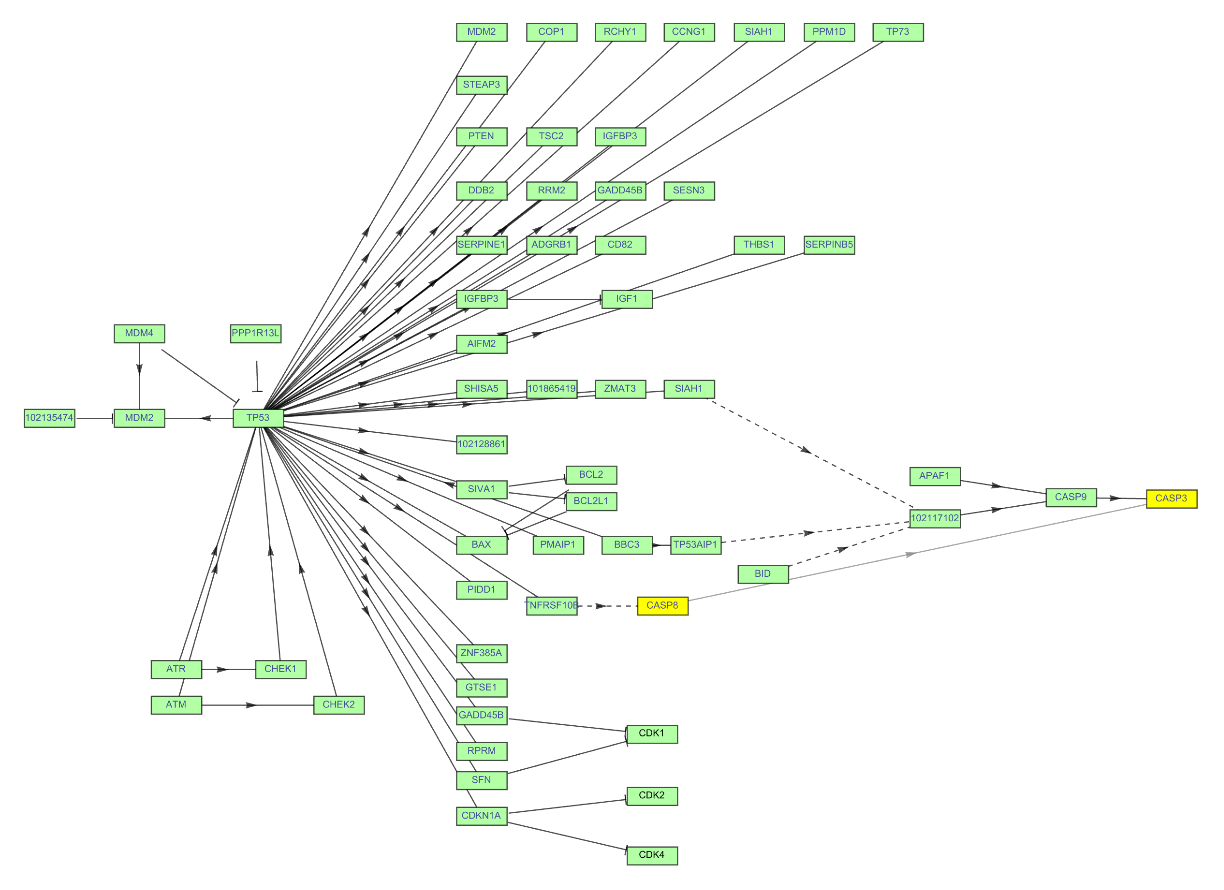

Get the Graph of the p53 signaling pathway of a macaque. Get the complete names of the path components hovering over them. Click the vertex name to get more information:

| In[10]:= | ![ResourceFunction["KEGGPathway", ResourceVersion->"1.2.1", ResourceSystemBase -> "https://www.wolframcloud.com/obj/resourcesystem/api/1.0"][

Entity["TaxonomicSpecies", "MacacaFascicularis::3cnwm"], "p53 signaling pathway", "Graph", VertexSize -> {0.015, .008}, VertexStyle -> Hue[0.31, 0.35, 1], VertexLabelStyle -> Directive[FontFamily -> "Arial", 8]]](https://www.wolframcloud.com/obj/resourcesystem/images/c26/c26fb78f-9391-4e5b-8348-1b3a9bcb8293/1-2-1/49dac638d19a93bf.png) |

| Out[10]= |  |